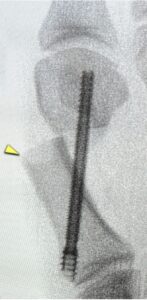

The pseudo bunion that results is at the yellow arrow above. These type of screws can cause a blowout metatarsal.

Stay away from surgeons that profess to do minimal incision surgery using these types of screws. They can be extremely detrimental to you.